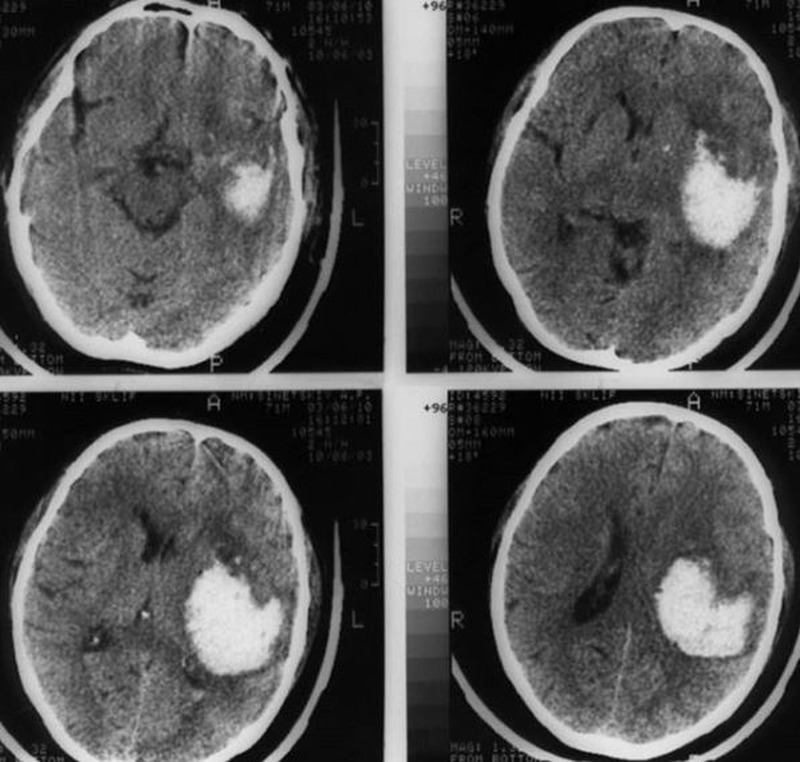

Ишемический инсульт левой стороны: симптомы и реабилитация